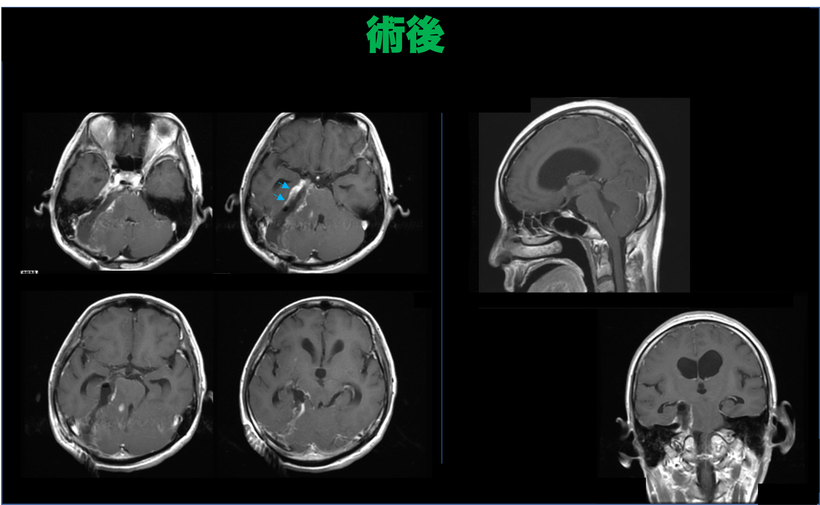

術後

右目がほぼ失明した状態で手術を行なった62歳女性の髄膜腫の症例 術後頭部MRI画像

直ちに手術(術中視覚への刺激モニターとナビゲーションシステムを使用)。全摘出にて術後7日目に合併症なく退院。視力は術後経過で完全に回復。

病理:WHO グレード-1、術後8年再発なし